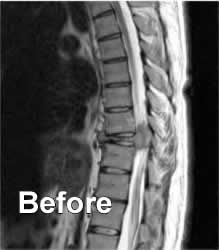

I was diagnosed with Solitary Plasmacytoma of Bone in early 2004.  By the time it was caught in MRI scans, my 9th thoracic vertebrate was completely obliterated.  I could barely walk and was losing feeling from the waist down.  In November 2004, I had an 11-hour operation to restore my spine using bone grafts and titanium implants, and began radiation treatments shortly thereafter.  I have 95% of my mobility back, 100% feeling in my legs again, and I now do bone surveys, blood tests and bone marrow biopsies every 3 months or so to determine if my Solitary Plasmacytoma has developed into Multiple Myeloma.  Like Randi, I owe my life to very talented, and dedicated medical professionals.  I owe my life to science.

Firstly, I want to address the clique of “alternative therapists” that advocate magnet therapy.  The average power of a kitchen magnet’s magnetic field, if of high quality, is roughly 1000 gauss (.1 tesla.)  These magnets sold as bracelets, rings, or pendants are said to cure chronic pain of muscles and bones.  The average MRI (Magnetic Resonance Imaging) scan has a magnetic field power of 30,000 gauss (3 tesla.)  Here is the MRI scan of my spine before the surgery:

I can assure you, I was still in pain after that MRI.  If I wasn’t cured of pain after that, surely it follows that a kitchen magnet is not actually relieving pain.  The power of suggestion to temporarily relieve symptoms is known as the Placebo Effect.  In the long run, placebo does nothing.